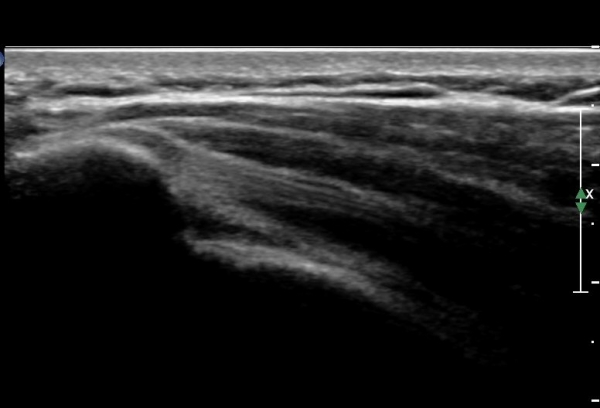

ÀÌµÎ¹Ú±Ù°Ç ±ÙÀ§ºÎȾ´Ü¸é°Ë»ç¿¡¼­ À̵ιڱٰÇÀÇ ³»ÃøÀ¸·Î ÀüÀ§°¡ °üÂûµÊ(»çÁø 5).